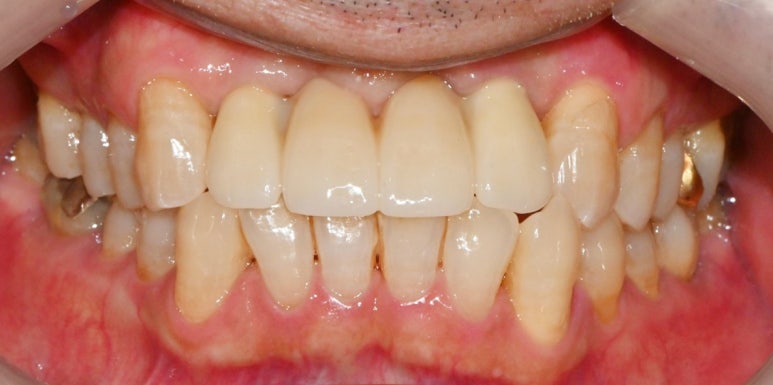

이전에 삐뚤었던 앞니가

고르게 바뀐 것이 보이시나요?

이전과 달리 배열이 고르게 바뀌면서

환자 스스로 양치하시기에도

훨씬 편해지셨을 것 같습니다.^^

또한 치조골의 질과 양이 좋은 곳에

지지 역할을 할 픽스처를

단단하게 잘 심어드렸기에

안정감도 더 크실 거라 생각합니다.